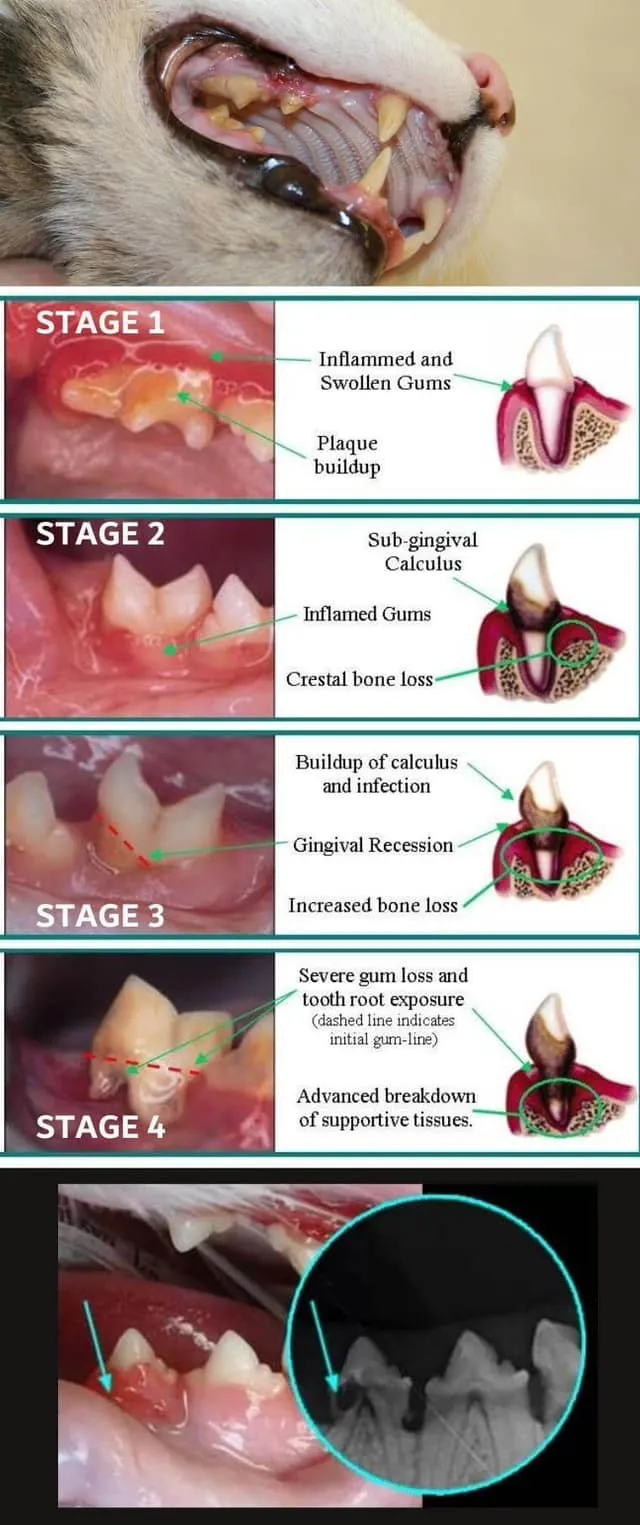

當我們檢查時,只看到牙齦嚴重增生,幾乎把牙齒全部埋住,輕輕碰觸就會滲血。

這類疾病在年幼貓常見,屬於複合性口腔疾病,無法單靠藥物或等待自行好轉。若放任不管,很容易惡化為牙周病或慢性口炎,造成骨質流失、牙齒鬆脫甚至喪失。

我們立即安排完整牙科檢查與治療(COHAT),利用口腔X光確認受損情況。手術中以雷射切除增生牙齦,但因發炎嚴重,仍有多顆恆齒必須拔除。術後配合抗生素、消炎與免疫調節治療,再加上飼主持續的居家刷牙照護,幾次回診後,情況才逐漸穩定。

這類疾病在年幼貓常見,屬於複合性口腔疾病,無法單靠藥物或等待自行好轉。若放任不管,很容易惡化為牙周病或慢性口炎,造成骨質流失、牙齒鬆脫甚至喪失。

我們立即安排完整牙科檢查與治療(COHAT),利用口腔X光確認受損情況。手術中以雷射切除增生牙齦,但因發炎嚴重,仍有多顆恆齒必須拔除。術後配合抗生素、消炎與免疫調節治療,再加上飼主持續的居家刷牙照護,幾次回診後,情況才逐漸穩定。